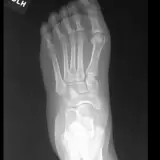

Over 2,100 interactive radiology cases, curated by radiologists for your level of training. Scroll, window, and view cases full screen — just like on PACS. Click linked findings in each writeup to jump straight to them on the image. Cases include sample reports, a focused discussion section, original illustrations, and videos.

PACSで期待されるツールを完備した完全インタラクティブな症例 — スクロール、ウィンドウ調整、ズーム、パン、計測、ROI、フルスクリーンモード。

重要な所見を症例画像上に直接ハイライトする豊富なアノテーション。症例解説内のリンクされた所見をクリックすると、スキャン上の正確な位置へジャンプできます。

職場のPACSステーションと同じようにスクロール、パン、ウィンドウ調整、ズームが可能